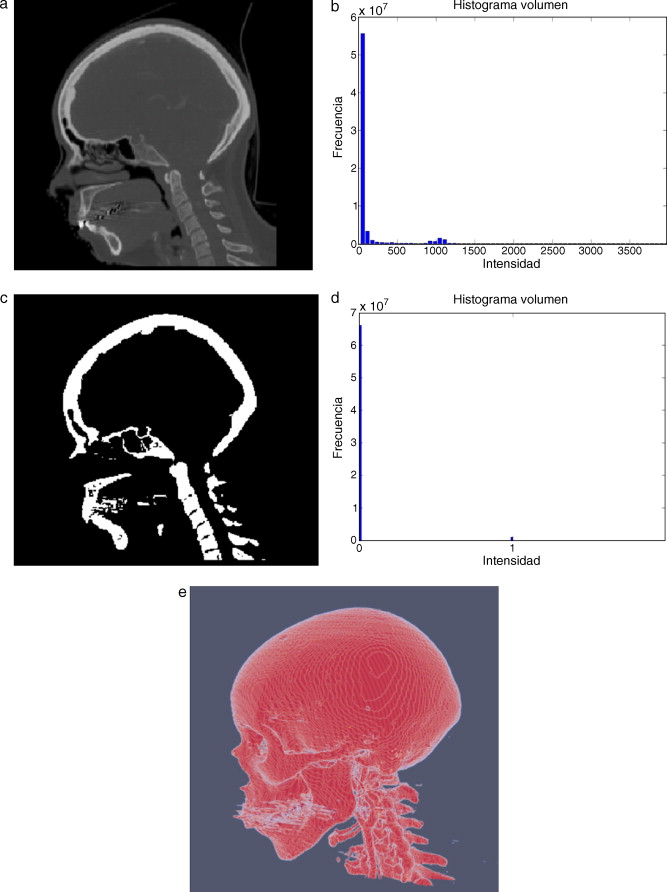

En la figura 9 se presenta el resultado de aplicar la rutina de umbralización global a una imagen tridimensional reconstruida a partir de imágenes de TC cráneo-facial, para segmentar el hueso del cráneo del background y los demás tejidos. En la figura 9 .b se presenta el histograma del volumen total de la figura 9 .a, en el cual se observan varios picos. La aplicación de esta rutina consistió en seleccionar el valor del umbral T igual a 1.235, asignándose el valor de 0 (negro) a aquellos voxels menores a T un umbral de valor 1.235. A los voxels con valores mayores o igual a T se les asignaron el valor 1 (blanco). De esta manera se obtuvo una nueva imagen binaria donde se ha segmentado el hueso cráneo-facial y parte de las vértebras ( fig. 9 .c). El histograma de esta nueva imagen binaria es presentado en la figura 9 .d y la vista 3D del hueso segmentado es presentada en la figura 9 .e.

Técnica de umbralización aplicada a imágenes de TC cráneo-facial. (a) Vista ...

Figura 9.

Técnica de umbralización aplicada a imágenes de TC cráneo-facial. (a) Vista original de un corte sagital. (b) Histograma de imagen a. (c) Imagen resultante de umbralizar imagen (a) con un umbral T = 1235. (d) Nuevo histograma de la imagen binaria (c). (e) Vista 3D del volumen del hueso cráneo-facial y parte de las vértebras segmentado con umbralización.